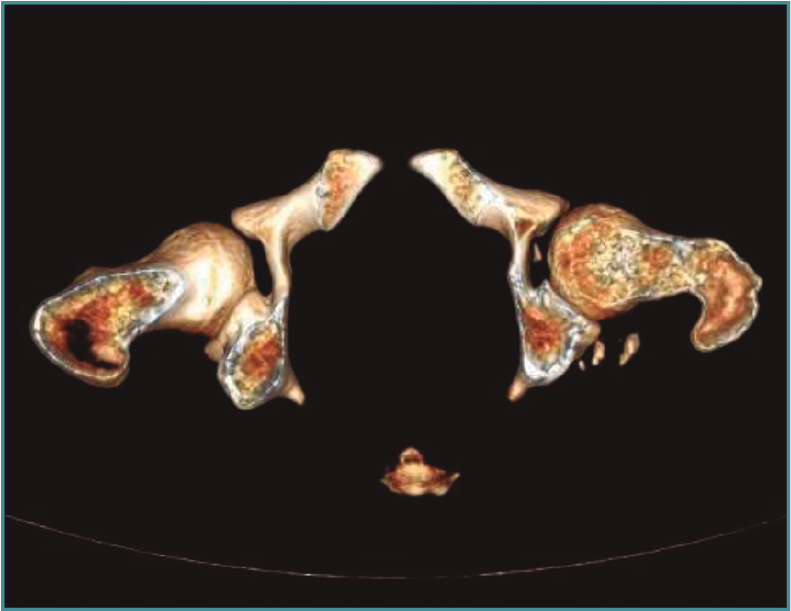

Se trata de un varón de 29 años que sufre una luxación posterior de cadera izquierda tras la caída de una lancha acuática de 1.600 kg sobre su miembro inferior. Se trata mediante reducción cerrada de cadera dentro de las 6 primeras horas posteriores a la luxación. La reducción fue satisfactoria, pero la TC muestra la presencia de fragmentos intraarticulares (Figura 1). Se le realizó tratamiento artroscópico de cadera con extracción de fragmentos (Figura 2).

Figura 1. Tomografía computarizada postoperatoria donde se aprecia la presencia de fragmentos óseos intraarticulares.